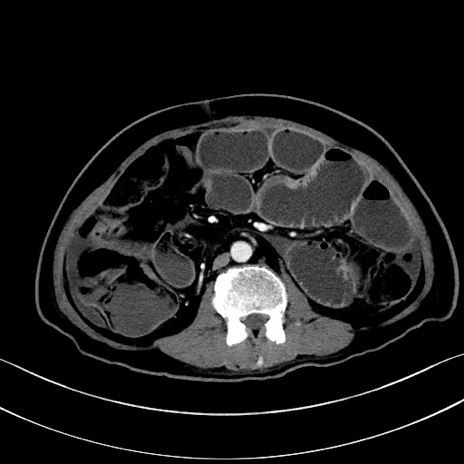

症例28(横断像)

【症例】60歳代男性

【主訴】嘔吐

【現病歴】胃癌にて胃全摘後。食思不振が悪化し、夜中に嘔吐することがある。

【既往歴】胃癌、胃全摘、脾摘、胆摘後

【データ】WBC 5900、CRP 10.56